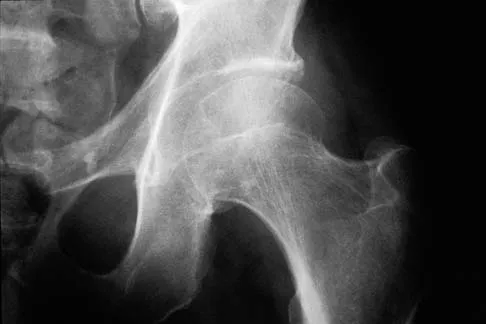

Figure 11 shows the radiograph of a 26-year-old man with type I diabetes mellitus who was struck by a motor vehicle. What is the most common complication associated with this pelvic fracture?

Explanation

The most common complication following acetabular or pelvic ring injury is deep venous thrombosis (DVT). Without prophylaxis, rates of DVT are as high as 70% to 80%. With prophylaxis, the rates are around 10%. Infection rates in surgical repair of acetabular fractures are relatively low but a history of diabetes mellitus and a significant Morel-Lavalle lesion certainly increase the risk. However, even with these two complicating factors, the rates of infection are still lower than 10%. Sciatic nerve palsy rates from the injury alone approach 20% and iatrogenic injury is usually less than 2%. Degenerative changes to the hip following this injury approach 20% to 25%, even with an anatomic reduction. Geerts WH, Code KI, Jay RM, et al: A prospective study of venous thromboembolism after major trauma. N Engl J Med 1994;331:1601-1606.